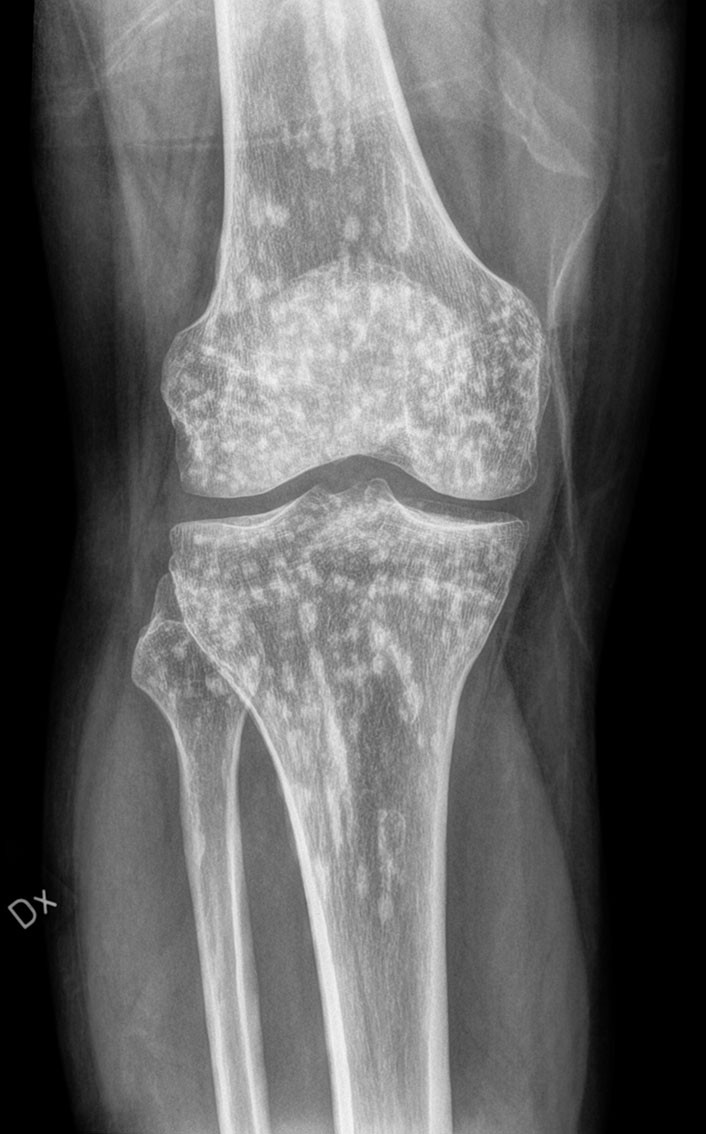

Røntgenbildet viser multiple flekkvise sklerotiske lesjoner i både femur, tibia og fibula. Bildet ble tatt da en tidligere frisk mann i slutten av trettiårene oppsøkte ortopedisk skadepoliklinikk etter et fall med vridning av kneet. Han kunne på dette tidspunktet ikke belaste det vonde benet, og opplevde at en bøyd knestilling ga mindre ubehag. Pasienten ble henvist til akutt røntgen for å utelukke brudd. Røntgenfunnet er forenlig med osteopoikilose og tolkes som et tilfeldig funn, ikke relatert til pasientens aktuelle skade. Pasientens smertetilstand i kneet gikk over av seg selv uten aktive tiltak.

Osteopoikilose er en benign autosomal dominant tilstand man kan finne i skjelettet, karakterisert av områder med små sklerotiske lesjoner (1). Osteopoikilose finnes oftest i de lange rørknoklene, i hender og føtter, i bekkenet og i skulderbladene. Tilstanden er sjelden, med en insidens på 1: 50 000 (2). Den oppstår like hyppig hos kvinner og menn, og gir vanligvis ingen symptomer. Tilstanden progredierer ikke til malignitet, og påvirker ikke skjelettkvaliteten. Det er ikke nødvendig med MR-undersøkelse for å stille diagnosen. På en eventuell MR vil lesjonene ha lav signalintensitet, både på T1- og T2-vektede bilder, og dermed fremstå som svarte flekker.